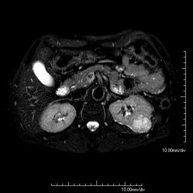

Prueba diagnóstica no invasiva que consiste en la obtención de imágenes de alta definición anatómica de la pelvis masculina mediante el empleo de un campo electromagnético y ondas de radio (con un emisor y un receptor). No utiliza radiación ionizante. No requiere de preparación previa. En algunas ocasiones requiere el empleo de contraste paramagnético (Gadolinio) para caracterizar las lesiones. Esta prueba permite valorar órganos como la vejiga urinaria, la unión entre los uréteres y la vejiga, la próstata, las vesículas seminales, la uretra, los huesos de la pelvis, etc.

Prueba diagnóstica no invasiva que consiste en la obtención de imágenes de alta definición anatómica de la glándula prostática mediante el empleo de un campo electromagnético y ondas de radio (con un emisor y un receptor). No utiliza radiación ionizante. Se utiliza una bobina endorrectal para obtener imágenes de máxima definición anatómica de la próstata, que permitirá realizar el estudio espectroscópico (estudio a nivel molecular que ayuda a diferenciar las células de origen maligno o tumoral). También se realiza el estudio con contraste paramagnético que aporta una mejor definición tisular. Esta prueba dura unos 40 minutos, durante los cuales el paciente deberá estar lo más quieto posible. Como preparación previa requiere limpieza del colon. Esta prueba está especialmente indicada en aquellos pacientes con sospecha de neoplasia de próstata, con neoplasia de próstata conocida para el estadiaje tumoral, estudio de localización del tumor prostático como guía o mapa para la biopsia, seguimiento de los pacientes con neoplasia de próstata tratados con tratamiento quirúrgico o radioterápico, sospecha de recidiva de la neoplasia de próstata, etc. - RM Cuerpo entero (Total body)

Prueba diagnóstica no invasiva que consiste en la obtención de imágenes de alta definición anatómica de la región escrotal mediante el empleo de un campo electromagnético y ondas de radio (con un emisor y un receptor). No utiliza radiación ionizante. En ocasiones se deberá emplear contraste paramagnético (Gadolinio) para completar el estudio. Se utiliza para el estudio detallado de los testículos, para identificar posibles tumores u otras patologías, además de poder visualizar alteraciones de las estructuras adyacentes. - RM Peneana